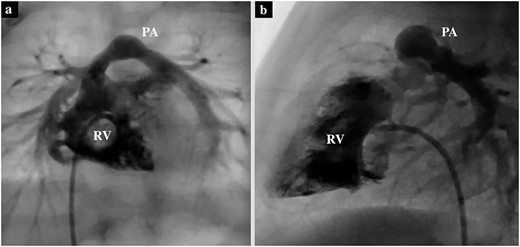

A male infant with TGA accompanied by Shaher Type 4 coronary anatomy underwent ASO at 5 days of age. Intraoperatively, the right ventricular outflow tract was injured during the RCA separation to obtain the mobilization and repaired using an autologous pericardial pledget, resulting in postoperative subvalvular PS. Follow-up evaluation showed relief of the subvalvular PS, but pulmonary valve stenosis, main pulmonary artery (PA) stenosis and right PA stenosis progressed because of the subvalvular jet. Transthoracic echocardiography showed a trans-right ventricle (RV) outflow peak velocity of 4.5 m/s, a systolic pressure gradient of 83 mmHg and a right ventricular fraction area change of 46.4% (Fig. 1). Cardiac catheterization showed a right ventricular pressure of 97 mmHg, a right ventricular/left ventricular pressure ratio of 0.99 and a systolic pressure gradient across the right ventricular outflow of 91 mmHg. The diameter of the pulmonary valve annulus was 6.1 mm (63.6%) (Fig. 2). Three-dimensional-computed tomography showed that the distance between the RCA and the tricuspid valve was 7 mm (Fig. 3).

Preoperative cardiac catheterization of the axial view (a) and sagittal view (b) showing PS, with the pulmonary valve annulus diameter of 6.7 mm.